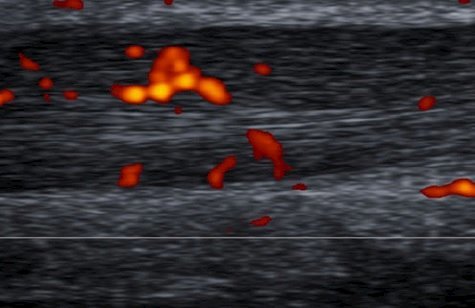

Buono et al in a 2013 paper entitled Achilles tendon function: functional anatomy and novel emerging models of imaging classification, were among the first to propose an image-based classification of Achilles tendon injuries. (1) The goal of their paper was to create a degree of prognostic value with a classification based on US and MRI. Their paper proposes a classification of Achilles tendon injuries based on anatomy of the tendon, symptoms, clinical findings and histopathology. The authors used MRI to define structural changes in the tendon with 96% sensitivity and color Doppler with reported 86% sensitivity. (2) Their classification was twofold. First, they used MRI to define structural alterations of the tendon. Secondly, they used color Doppler to define the degree of reactive revascularization surrounding the tendon. Increased revascularization suggested not only a response to injury but also provided an opportunity to prognosticate regarding the success of the response to injury - increase vascularization suggested a potentially successful outcome, whereas lack of revascularization suggested a poor outcome.